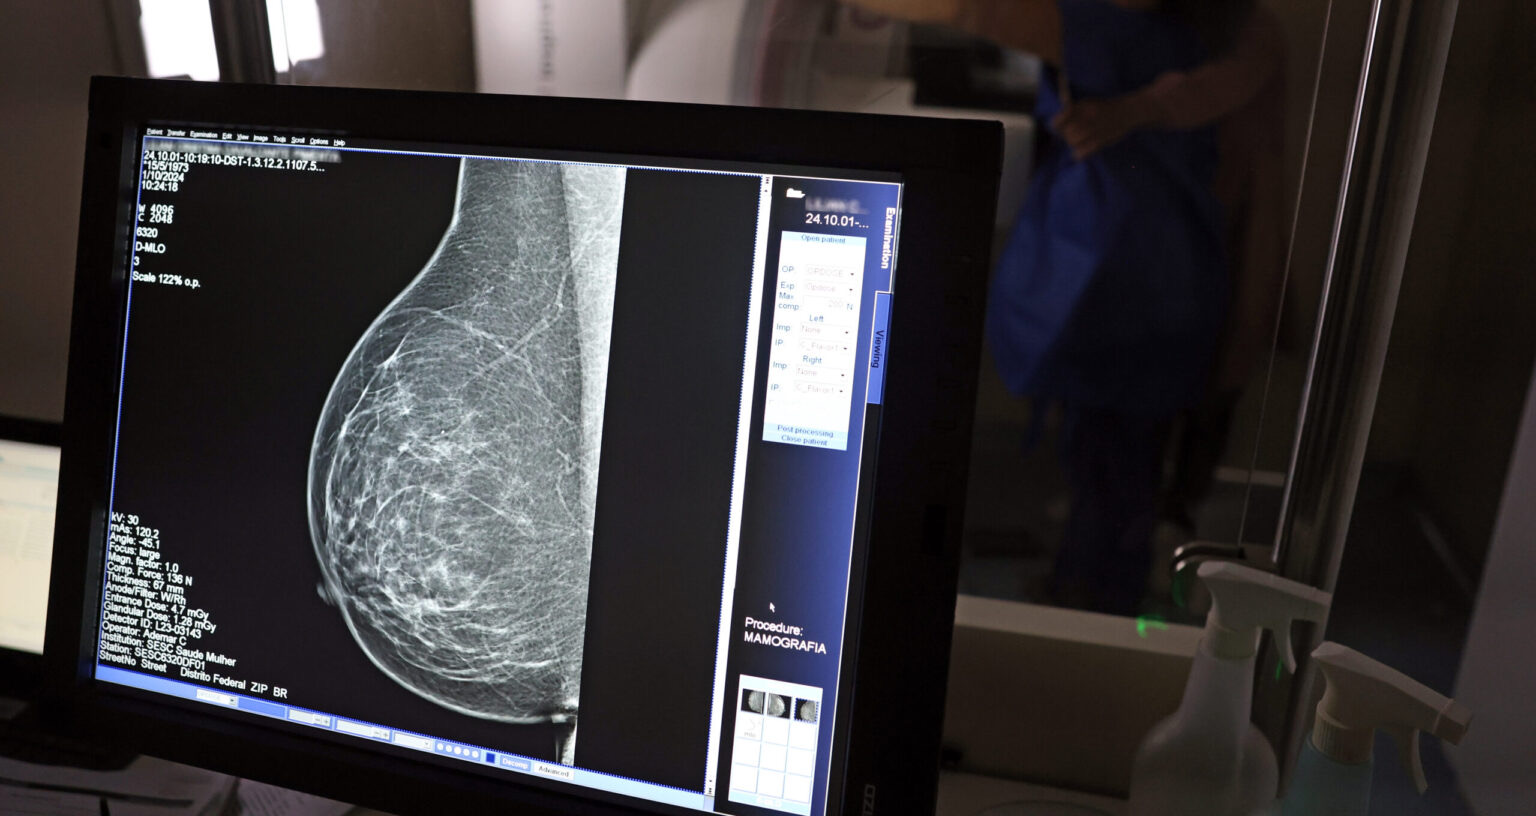

Foto: José Cruz/Agência Brasil

Com mais de 57 mil mamografias realizadas em 2025, o Piauí ampliou significativamente o acesso ao diagnóstico precoce do câncer de mama, especialmente entre mulheres a partir dos 40 anos. Como parte das ações de reforço ao tratamento, o estado recebeu, na quinta-feira (23), uma remessa com 224 unidades do medicamento Trastuzumabe Entansina, recém-incorporado ao Sistema Único de Saúde (SUS) para casos avançados da doença.

A rede estadual conta com 43 mamógrafos fixos e o serviço itinerante dos Caminhões da Mamografia, que percorrem os municípios levando o exame a quem mais precisa. O foco principal tem sido nas mulheres entre 40 e 49 anos, faixa etária que passou a ser atendida sob demanda, conforme nova orientação do Ministério da Saúde.

A técnica em radiologia Ana Vitória atua na Central de Diagnóstico de Valença e confirma o impacto direto na vida da população. “Antes o exame só era disponibilizado em clínica particular. Agora, mulheres de toda a região vêm aqui, fazem o agendamento e realizam o exame. Atendemos mulheres a partir dos 40 anos, sem fila, com estrutura pública. Isso melhorou muito a vida das pessoas”, afirma.